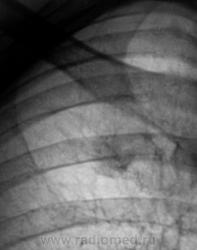

За год "штучка" подросла.

И стала периферическим раком? легкого. Думаю дифф ряд надо начать с этого.

Я тоже сначала подумал о "периферическом", но похоже, "обломался". Сейчас добавлю боковые томограммы.

На томограммах не получили изображение округлой тени. Возможно, она имеет отношение к грудной стенке?

Ничего боелее окостеневшего хряща 1-го ребра справа, как мне кажется...я уже упоминал о его "причудливости" и возможности ошибки...и даже без остеомы или остеохондромы...

А я вижу снижение прозрачности в верхушечном сегменте справа.